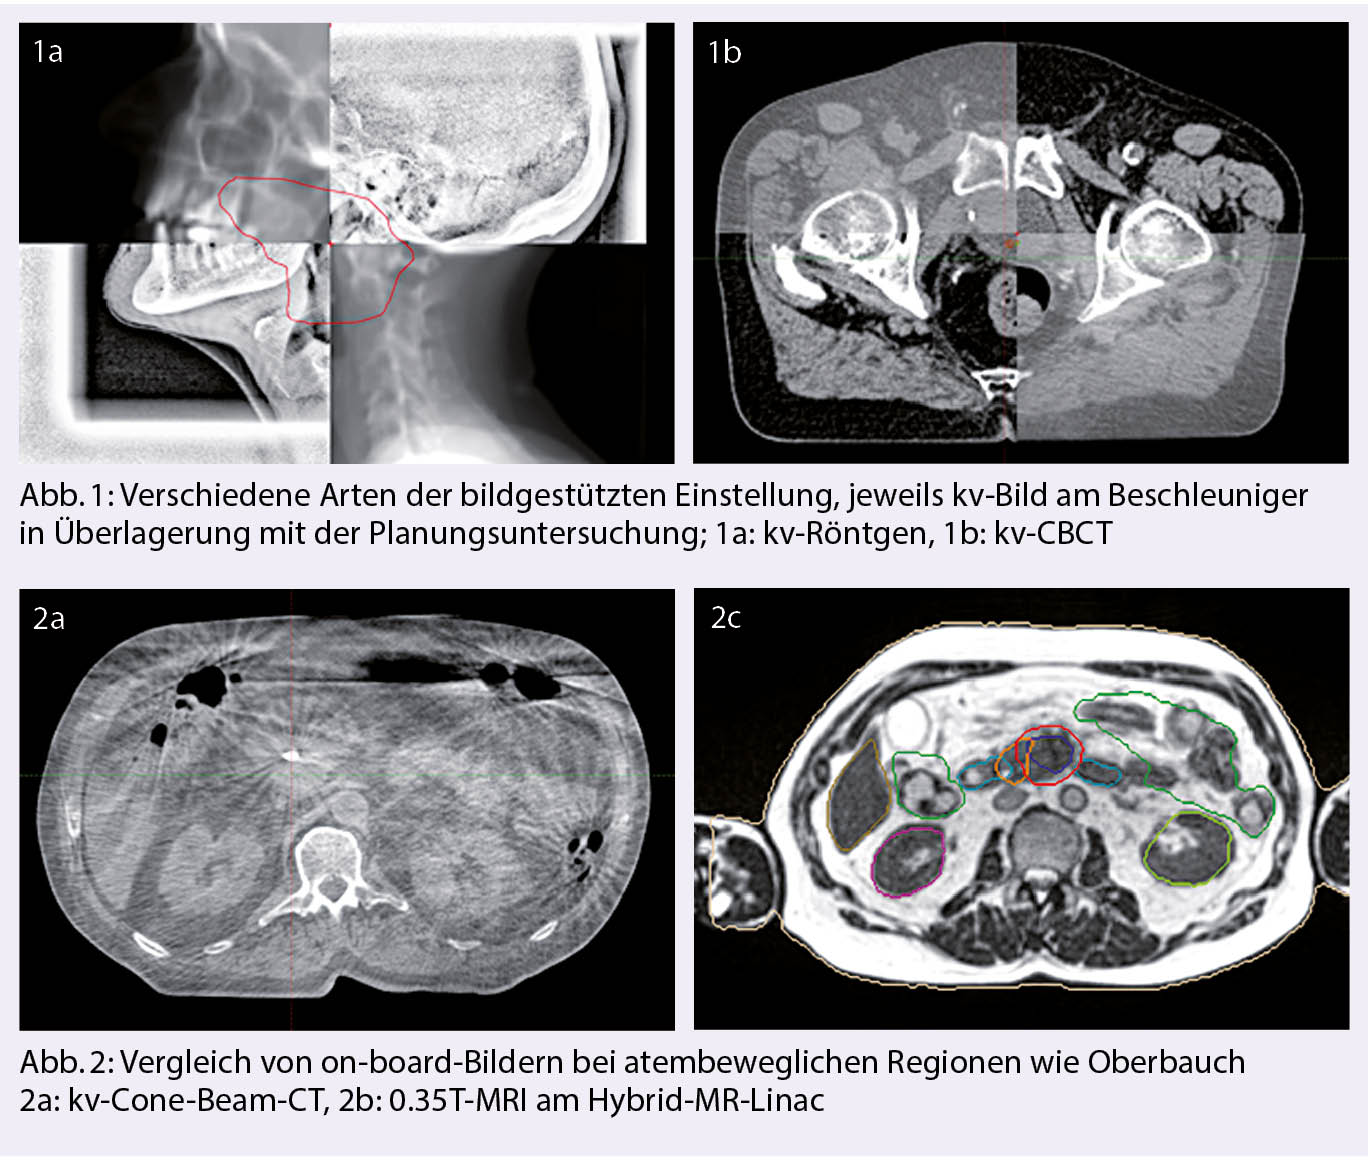

Ursprünglich erfolgte die Bildgebung mit Röntgenbildern, indem die knöchernen Strukturen in Übereinkunft gebracht wurden. Im 21. Jahrhundert kam die Entwicklung des heutzutage zum Standard gehörenden kv-Cone-Beam-CT (CBCT), bei dem mit einer Rotation einer an den Linearbeschleuniger angebrachten kv-Röhre ein CT generiert wird (Abb. 1). Dieses lässt neben der knöchernen Übereinstimmung auch bis zu einem gewissen Grad die Beurteilung der Weichteile und damit auch z.B. der inneren Organe wie Blase oder Darm zu. Diese sogenannte «Image Guided Radiotherapy» (IGRT) konnte sich in klinisch merkbar reduzierter Toxizität niederschlagen und legte den Grundstein für die Einführung von stereotaktischen Techniken (1).

Aktuell ist die SBRT für Tumore der Lunge im Frühstadium als Alternative zur Operation, sowie bei Lungen-, Leber- und Knochenmetastasen fest etabliert. Es können dabei lokale Kontrollraten von 80-90% nach 3 Jahren erreicht werden, sofern aufgrund von Grösse und Lage der Metastasen eine ablative Strahlendosis appliziert werden kann (5). Je nach Lokalisation reicht die Einstellung mittels CBCT aus, jedoch sind bei abdominellen Zielen auch Techniken zur Atemkontrolle und –Überwachung nötig. (Abb. 2)